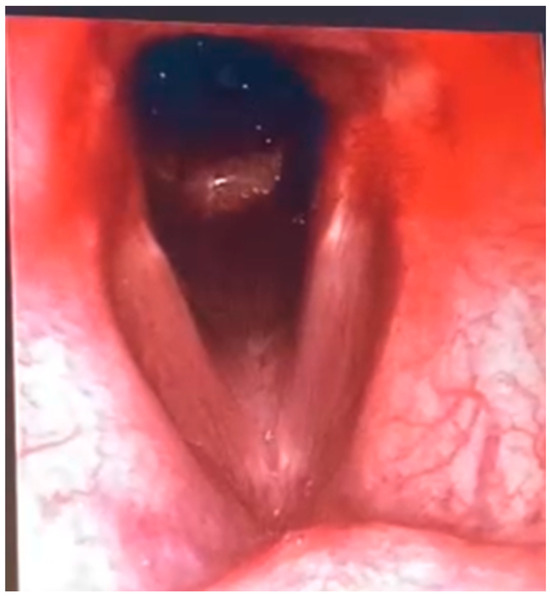

The videofibrolaryngoscopy in endoscopic view revealed a laceration of the posterior tracheal wall compatible with a tracheo-oesophageal fistula (TEF), with normal vocal cord mobility and an area of mucosal discontinuity posteriorly-typical of TEFs acquired due to prolonged pressure from a tracheostomy cuff and nasogastric tube (Figure 3). A bronchoscopy performed under sedation showed oedematous laryngeal structures with preserved motility, increased tracheal secretions, and a linear laceration of the posterior tracheal wall, confirming the diagnosis of tracheo-oesophageal fistula.

Figure 3. Endoscopic view from videofibrolaryngoscopy showing a laceration of the posterior tracheal wall compatible with tracheoesophageal fistula (TEF). The normal opening of the vocal cords is visible, and posteriorly, a discontinuity in the mucosal surface suggests a possible esophageal communication, typically seen in acquired TEFs due to prolonged pressure from tracheostomy cuffs and nasogastric tubes.

The availability of diagnostic tools such as bronchoscopy, videofluoroscopy, and sagittal neck CT allows for fast and accurate assessment. Additionally, weaning from mechanical ventilation should be considered a fundamental prerequisite for selecting surgical candidates, as evidenced by better clinical outcomes in non-ventilated patients. As demonstrated in our patient (Figure 2 and Figure 3), the integration of sagittal CT imaging with endoscopic evaluation enhances early detection of subtle posterior tracheal wall defects that may be missed on axial-only views. This combined anatomical–functional approach has also been emphasized in recent reviews [6,10]. Our case further confirms that structuring a standardized evaluative pathway centered on interdisciplinary collaboration not only improves surgical outcomes but also enables a more timely and targeted rehabilitative approach. Although mechanical ventilation is not an absolute contraindication, partial or complete weaning remains a key factor in surgical eligibility, reducing the risk of perioperative complications and enhancing tissue healing.